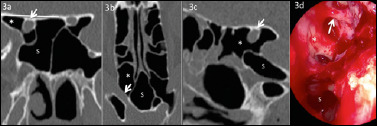

Abstract Image

Methods: In this study, 430 computed tomography scans of paranasal sinuses were analysed to establish the prevalence and different types of Onodi cells. Furthermore, the relationship between Onodi cell and different patterns of sphenoid sinus pneumatisation and surrounding structures were investigated. Special attention was paid to the relationship between Onodi cell and the optic nerve canal, particularly in cases when the optic nerve canal was bulging by more than 50% into the Onodi cell (Type IV).

Results: The Onodi cell was detected in 21.6% of cases, with the most common being Type I (48.5% right, 54.3% left). Type IV bulging of the optic nerve canal into the Onodi cell was observed in 47.1% of cases on the right side, 41.2% on the left side and bilateral in 11.7% of cases.